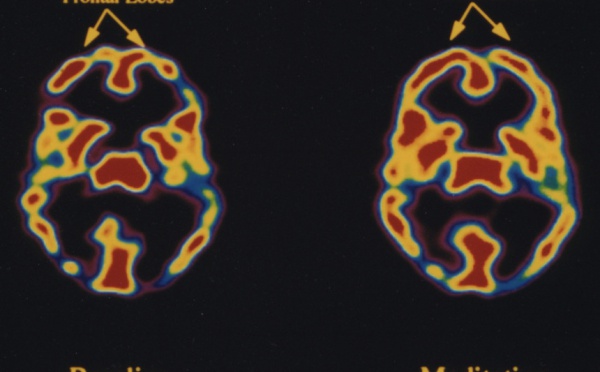

La neuroteología permitirá comprender la relación entre conciencia y mundo material - 16/02/2011

El neurocientífico Andrew Newberg reflexiona en un artículo reciente sobre el futuro a corto y largo plazo de la neuroteología, que es el estudio de las actividades neuronales relacionadas con experiencias de espiritualidad y religiosidad. Según Newberg, en los próximos años, esta disciplina permitirá comprender a fondo la neurología subyacente a la religiosidad humana, conectando así la biología con nuestras experiencias, sentimientos y creencias.

Es posible aprender neurológicamente la espiritualidad - 03/03/2011

Sin ánimo de meter bazas en la polémica entre ciencia y Fe, puede afirmarse que está más que probado el beneficio físico y espiritual que queda como remanente en las personas que vivieron una experiencia mística. Por lo tanto, es válido buscar la manera de entrenar esa percepción de lo trascendente como si fuera un músculo. Al respecto, los recientes estudios sobre plasticidad neuronal son un buen punto de partida para esta misión.